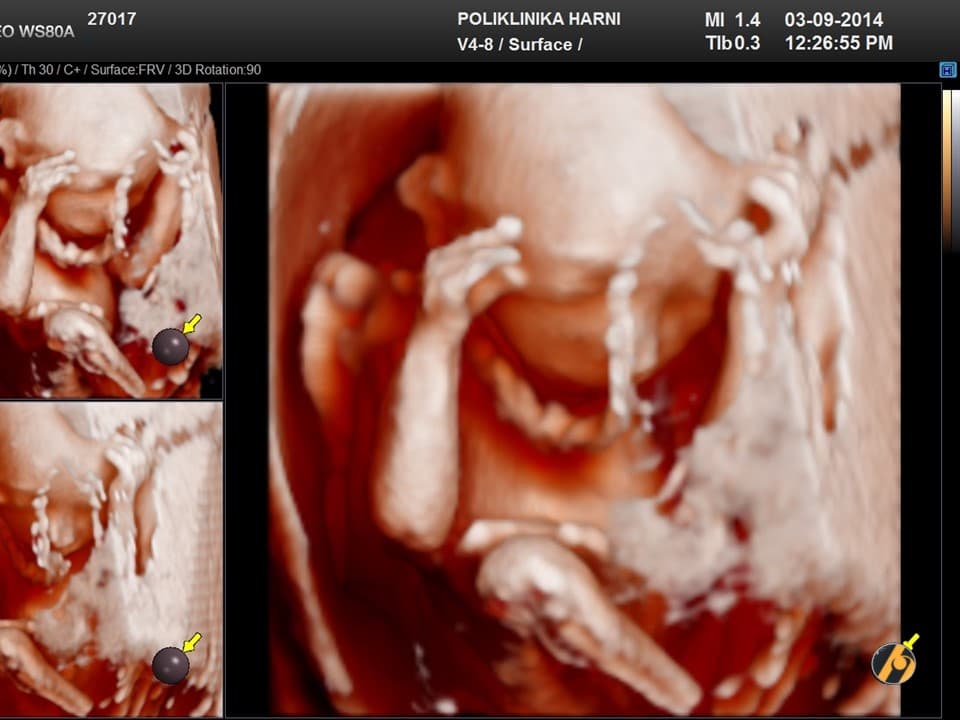

Nastavlja se finiji razvitak kože vaše bebe, koja je u ovo vrijeme tanka i prozirna i kroz koju se vidi mnoštvo krvnih žilica. Lanugo dlačice prekrivaju gotovo cijelu površinu kože bebe, a jasnije se ističu dlačice na obrvama. Počinje rasti kosa na glavi, a pigmentne stanice počinju stvarati crni pigment.

Razvijaju se daljnji centri okoštavanja i kosti, kao i koštana moždina koja preuzima funkciju žumanjčane vreće u stvaranju krvi djeteta. Zglobovi bebe su sve pokretljiviji, a beba s time i sve savitljivija. Sada vaša beba može svoje prstiće stisnuti u šaku.

Vaša beba guta amnijsku tekućinu koja ga okružuje, što pomaže sazrijevanju respiratornog sustava. Bebine oči su i dalje zatvorene, ali beba počinju reagirati na svjetlost izvan vaše maternice. Od ovog tjedna vaše će dijete početi čuti zvukove u vašem tijelu, poput otkucaja srca i trbuha.

Vaša beba dugačka je 10 - 12 cm, a teška 50 - 100 g.